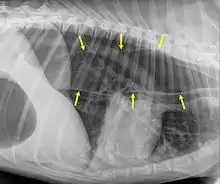

Megaesophagus, also known as esophageal dilatation, is a disorder of the esophagus in humans and other mammals, whereby the esophagus becomes abnormally enlarged. Megaesophagus may be caused by any disease which causes the muscles of the esophagus to fail to properly propel food and liquid from the mouth into the stomach (that is, a failure of peristalsis). Food can become lodged in the flaccid esophagus, where it may decay, be regurgitated, or maybe inhaled into the lungs (leading to aspiration pneumonia).[1]

An important distinction in recognizing megaesophagus is the difference between when a dog regurgitates or vomits. When a dog regurgitates there is usually not as much effort involved as when a dog vomits. Often when regurgitating, the dog will tip its head down and the liquid and/or food will almost appear to "spill out" of its throat.

One of the primary dangers to a dog with megaesophagus is aspiration pneumonia. Because the food stays lodged in the throat, it can often be inhaled into the lungs causing aspiration pneumonia. One way to avoid this is to make sure that every time the dog eats or drinks anything, that the dog sits for at least 10 minutes afterward or is held in a sitting up or begging position. This disorder has a guarded prognosis, however, a successful management technique is vertical feeding in a Bailey Chair.[8]